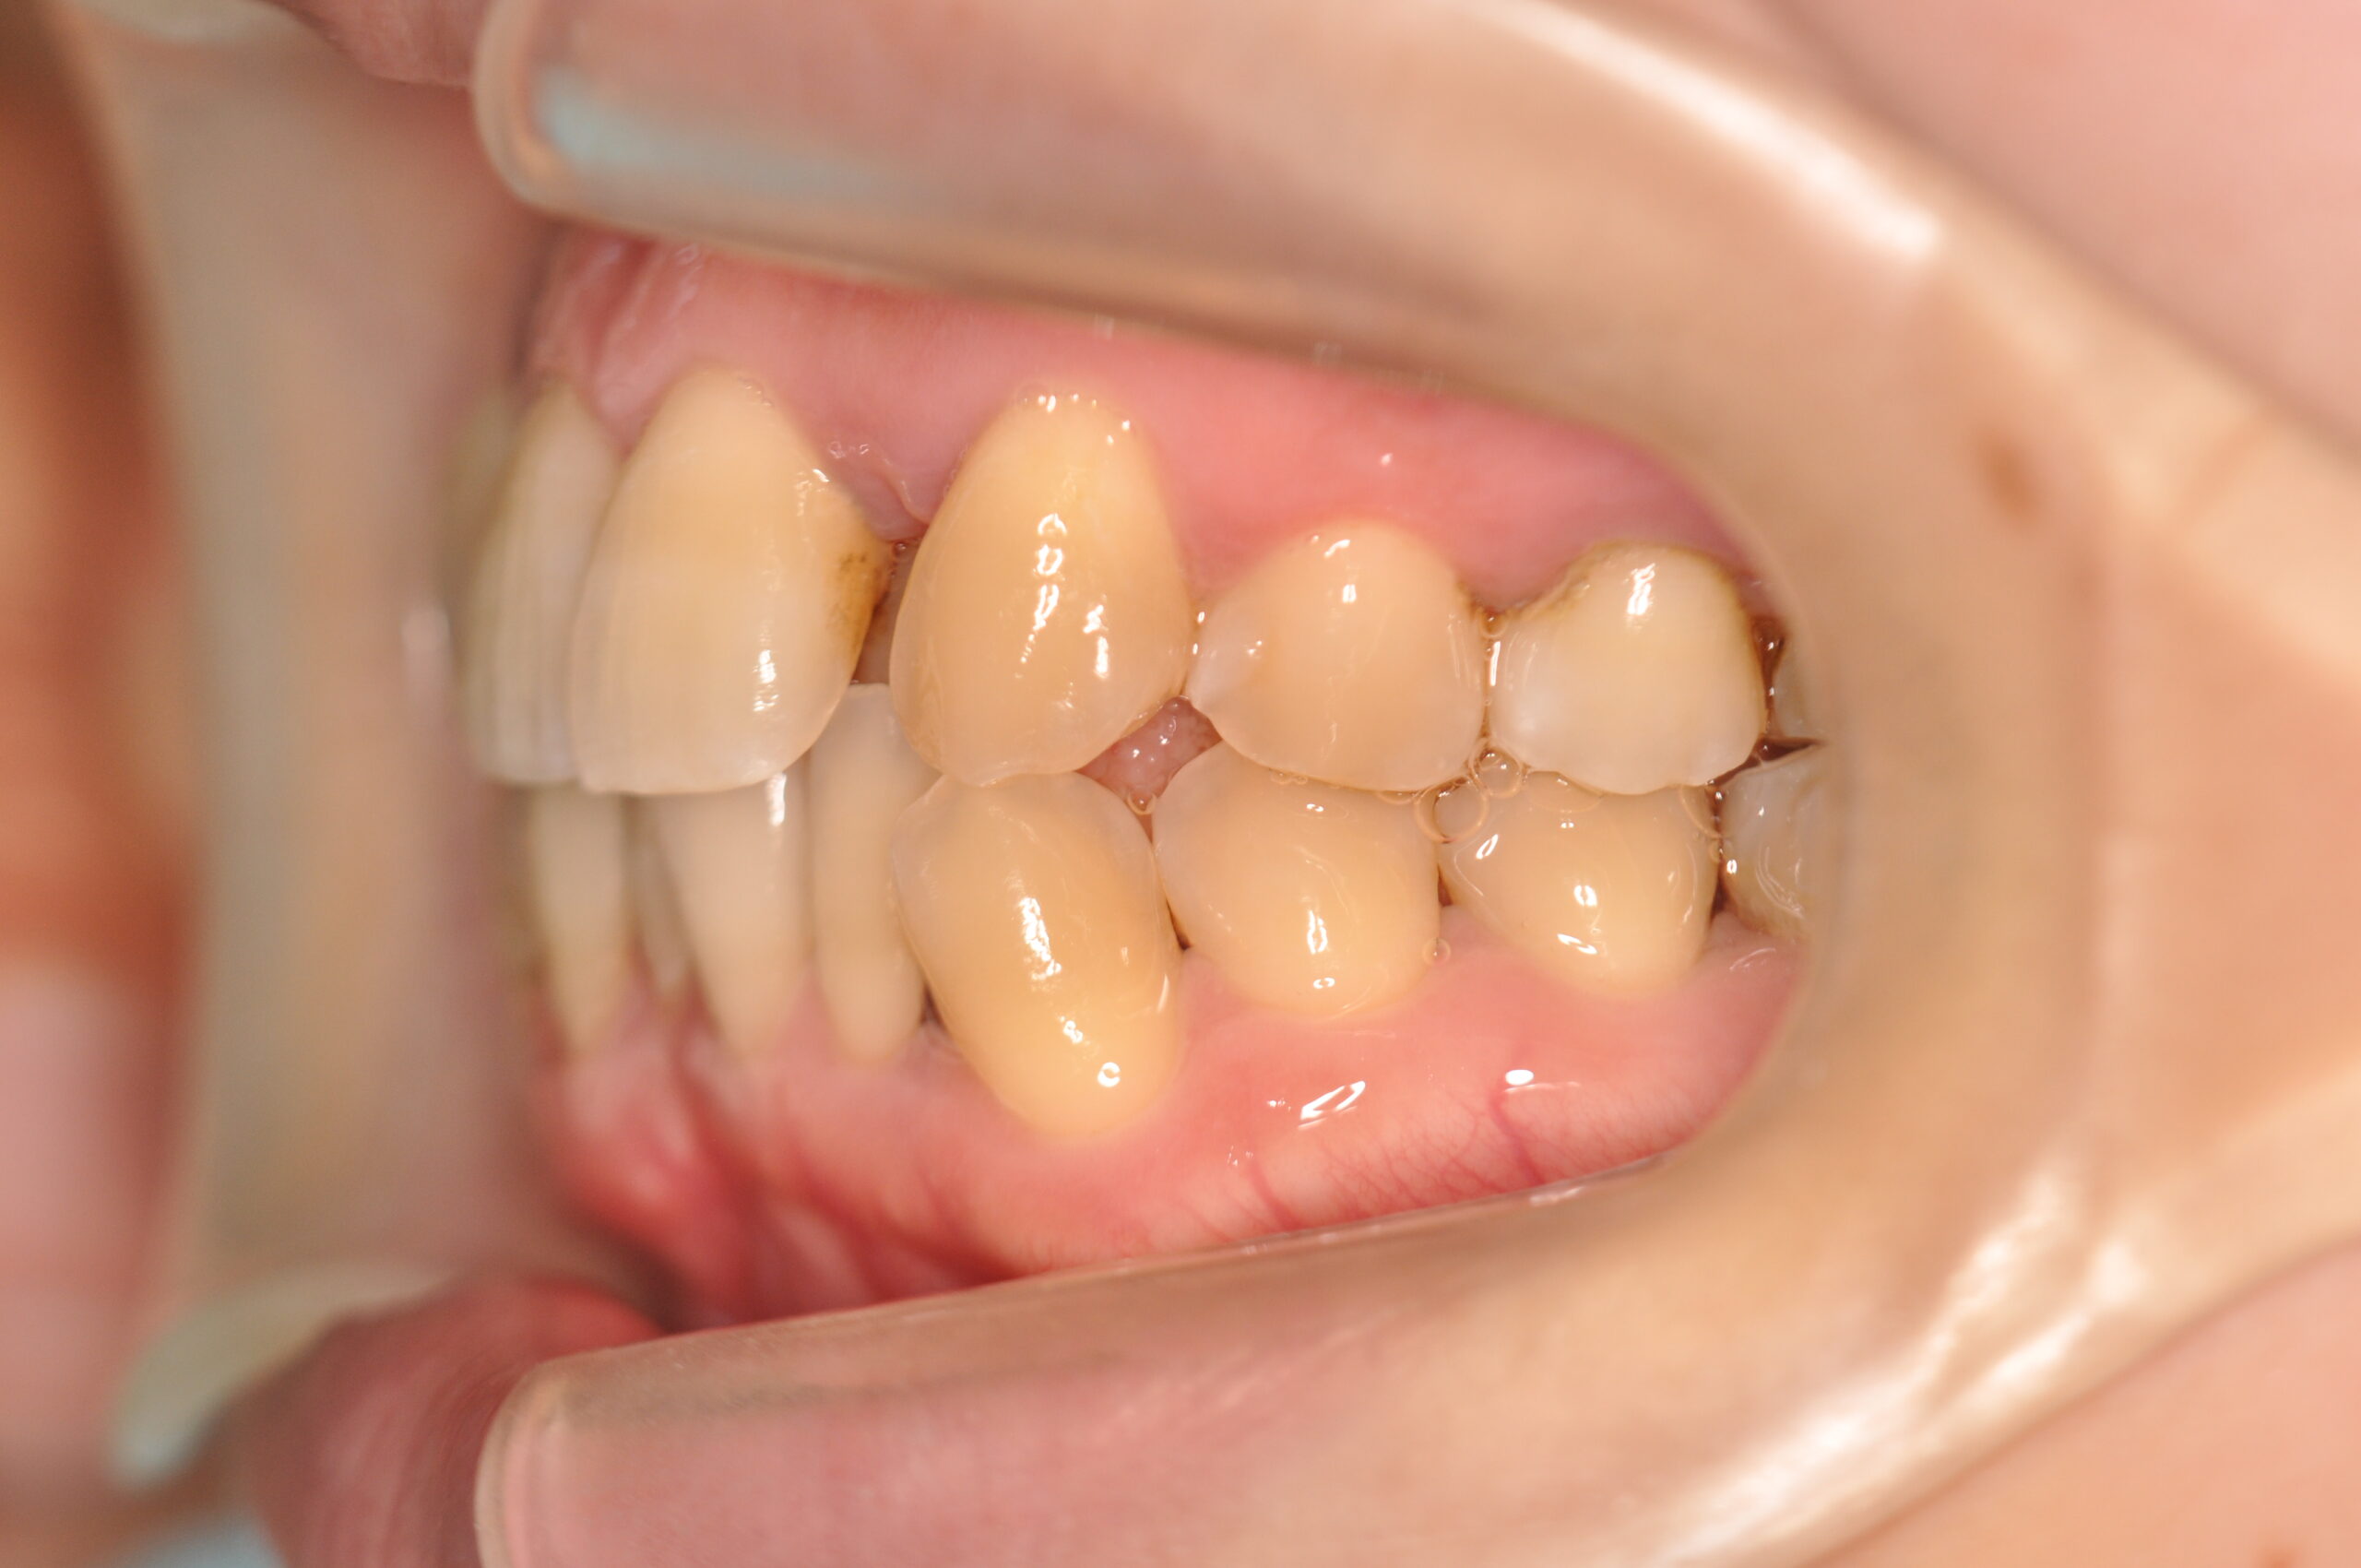

叢生(非抜歯)[2590]

初診時

年齢

31歳10ヶ月 性 別 女性

治療期間 2年7ヶ月 費 用 矯正施術料:1,000,000円 調整料:4,000円/月

治療内容の詳細 初診時31歳の女性で、前歯が奥側にあることを気にされ来院されました。

検査の結果、上下顎叢生を伴うアングルⅠ級不正咬合と診断しました。

治療としては、上顎臼歯部の遠心移動を行い、歯を配列するためのスペースを確保し、非抜歯の上、セルフライゲーションブラケット装置(デーモンシステム)で歯の配列と咬合関係の改善をを行いました。

治療期間は、2年7ヶ月でした。